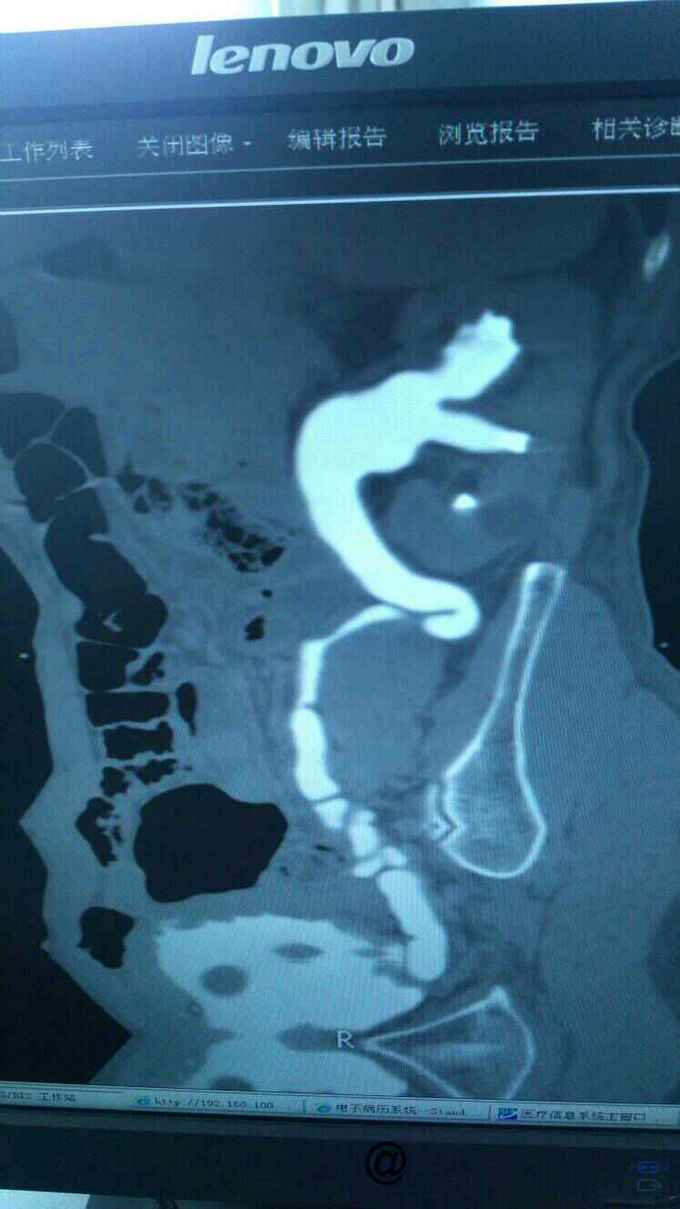

查膀胱镜发现后尿道狭窄,无法进入膀胱。 尿道造影:尿道狭窄,输尿管逆流。嘱咐病人排尿时,膀胱内尿液减少,进入输尿管,肾盂。 肾功能正常。

诊断:尿道狭窄,输尿管逆流 治疗:输尿管镜下探查,见尿道狭窄,膀胱内景清晰,广泛房小梁形成,右侧膀胱后壁可见广口凹陷,输尿管镜置入,可向上探查,实为输尿管,管腔宽大,输尿管镜进出自如,未见占位病变,向膀胱内置入导丝,沿着导丝留置导尿管扩张尿道。